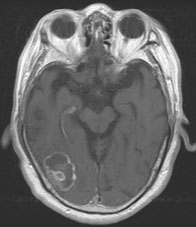

転移性脳腫瘍 肺癌の脳内転移

[ラジオサージャリー前]

CT(左画像): 左下の黒くなっているところが癌、 造影MR(右画像):左下の周りが白い線で囲まれたようになっているところが癌

[ラジオサージャリー後2ヵ月半]

CT、MRともに癌が縮小している。